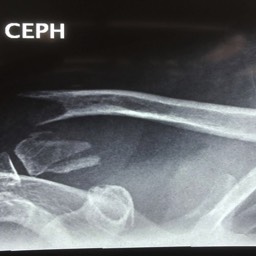

What do Distal Clavicle Fractures Look Like on X-ray and CT?

X-RAY

Click an image to enlarge